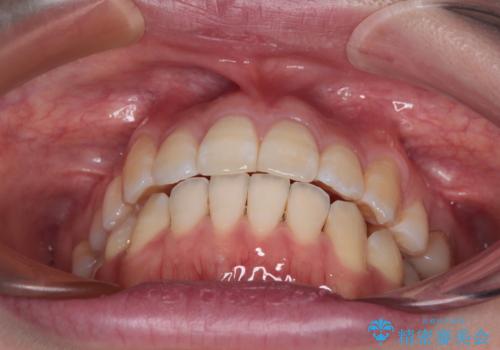

八重歯と開咬の抜歯矯正 ワイヤー装置を併用したインビザライン矯正治療

- 咬み合わない前歯と八重歯などのデコボコを気にして来院された患者様です。

上下前歯の位置を比較すると上顎が前方にあり、デコボコ改善でより上顎が前方に行く可能性があります。

開咬の改善にはインビザラインが有効であり、インビザライン単体での治療を検討しましたが、上顎前突を回避するために上顎左側第一小臼歯抜歯を行うこととしたため、補助装置とワイヤー矯正を併用した上で、インビザラインによる矯正治療を行うこととしました。